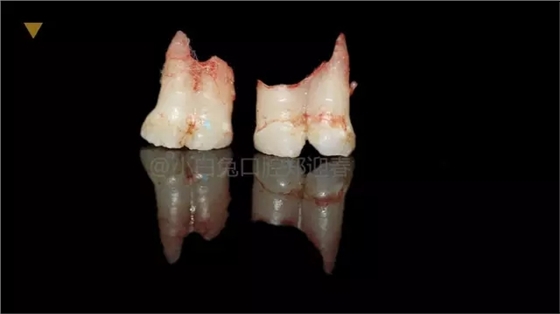

患兒,10歲,因上前牙未替換來(lái)診,查體:輕度反合,51和52、61和62均融合,且存在間隙約4mm,全面曲面斷層片顯示:11、21未萌,52、51、61、62牙根均有不同程度的生理性吸收。

拔出后的離體牙